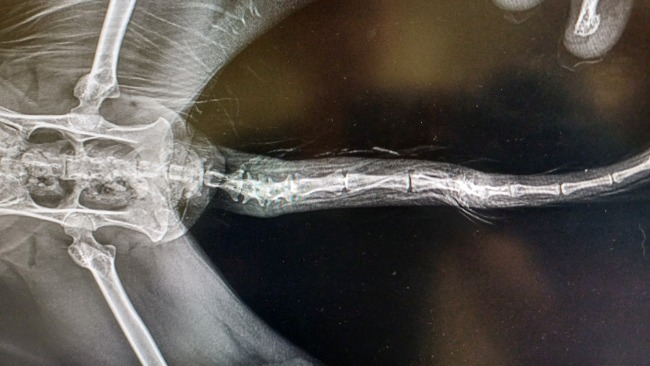

Nasz pierwszy cel zbiórki to 235 zł, na które mamy fakturę do opłacenia. Pysia była na koniecznym badaniu krwi przed zabiegiem oraz odrobaczaniu, bo jak okazało się mała ma ponownie problem z glistami. Na szczęście wszystkie wyniki krwi są w normie, więc Pysia jest gotowa na zabieg w środę!